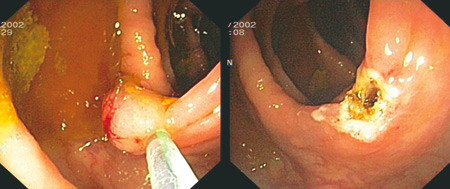

Små polypper under 3 – 4 mm vil kunne fjernes med stor biopsitang med én eller flere biopsitagninger. Alternativt kan man bruke «hot biopsy»-reseksjon (biopsi med varmekoagulasjon). Undersøkelser har vist viabelt gjenstående polyppmateriale i 17 % av prosedyrene ved denne metoden, og den innebærer en viss perforasjonsrisiko. Små slynger kan også brukes, og «kald giljotinering», dvs. at man river av polyppen uten koagulasjonsstrøm, har vist seg trygt ved små polypper (< 5 mm) (26). Polypper større enn 5 mm vil i de fleste tilfeller kunne fjernes med diatermislynge (fig 1). Ved store, stilkete polypper kan det injiseres fortynnet adrenalin i stilken eller brukes såkalt endoloop (en trådslynge som strammes rundt polyppen) i forkant for å redusere blødnings- og perforasjonsfaren (27).